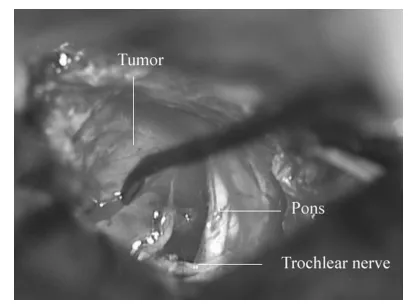

采用经岩前入路手术。行右颞开颅术,从中颅窝底抬起硬脑膜,保留岩浅大神经。磨除后内侧三角骨质,切开颞部及后颅窝硬脑膜,结扎岩上窦后切开窦壁及天幕。见肿瘤位于天幕缘下方,滑车神经位于肿瘤后下极,神经末端呈扇形与肿瘤融合,确认肿瘤起源于滑车神经(图2)。

图2.右经岩前入路术后术野所见。肿瘤起源于滑车神经,神经末端呈扇形与肿瘤融合。

肿瘤内含黄色囊液,与三叉神经无关联。未能窥及位于桥前蛛网膜后方的动眼神经与外展神经。因肿瘤与脑干边界清晰且未粘连重要血管,顺利分离周边结构后切断滑车神经实现肿瘤全切。